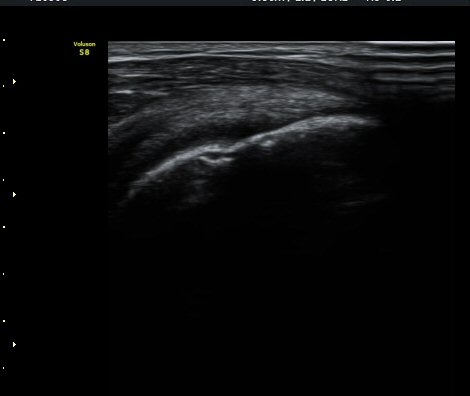

À­ÆÈÀ» ³»È¸Àü, ³»ÀüÇÑ »óÅ¿¡¼­ ±Ø»ó°Ç Á¾´Ü¸é°Ë»ç¿¡¼­ ±Ø»ó°Ç ³»Ãø¿¡¼­ ƯÀÌ ¼Ò°ßÀ» º¸ÀÌÁö

¾ÊÀ¸³ª(±×¸² 5) ±Ø»ó°Ç ¿ÜÃø¿¡¼­ ´ë°áÀý ÇÇÁú°ñ ¿¬°á¼º ¼Ò½ÇÀ» º¸ÀδÙ(±×¸² 6). ±ØÇ졂 Á¾´Ü¸é

°Ë»ç»ó(±×¸² 7) ƯÀÌ ¼Ò°ßÀ» º¸ÀÌÁö ¾Ê´Â´Ù. ±Ø»ó°Ç Ⱦ´Ü¸é °Ë»ç»ó ±Ø»ó°ÇÀÇ ±ÙÀ§ºÎ¿¡¼­´Â

ƯÀÌ ¼Ò°ßÀ» º¸ÀÌÁö ¾ÊÀ¸³ª(±×¸² 8) ±Ø»ó°Ç ¸»´ÜºÎÀ§¿¡¼­ ´ë°áÀýÀÇ °ñ °áÇ̰ú ÇÇÁú°ñ ¿¬°á¼º

¼Ò½ÇÀ» º¸ÀδÙ(±×¸² 9, 10).